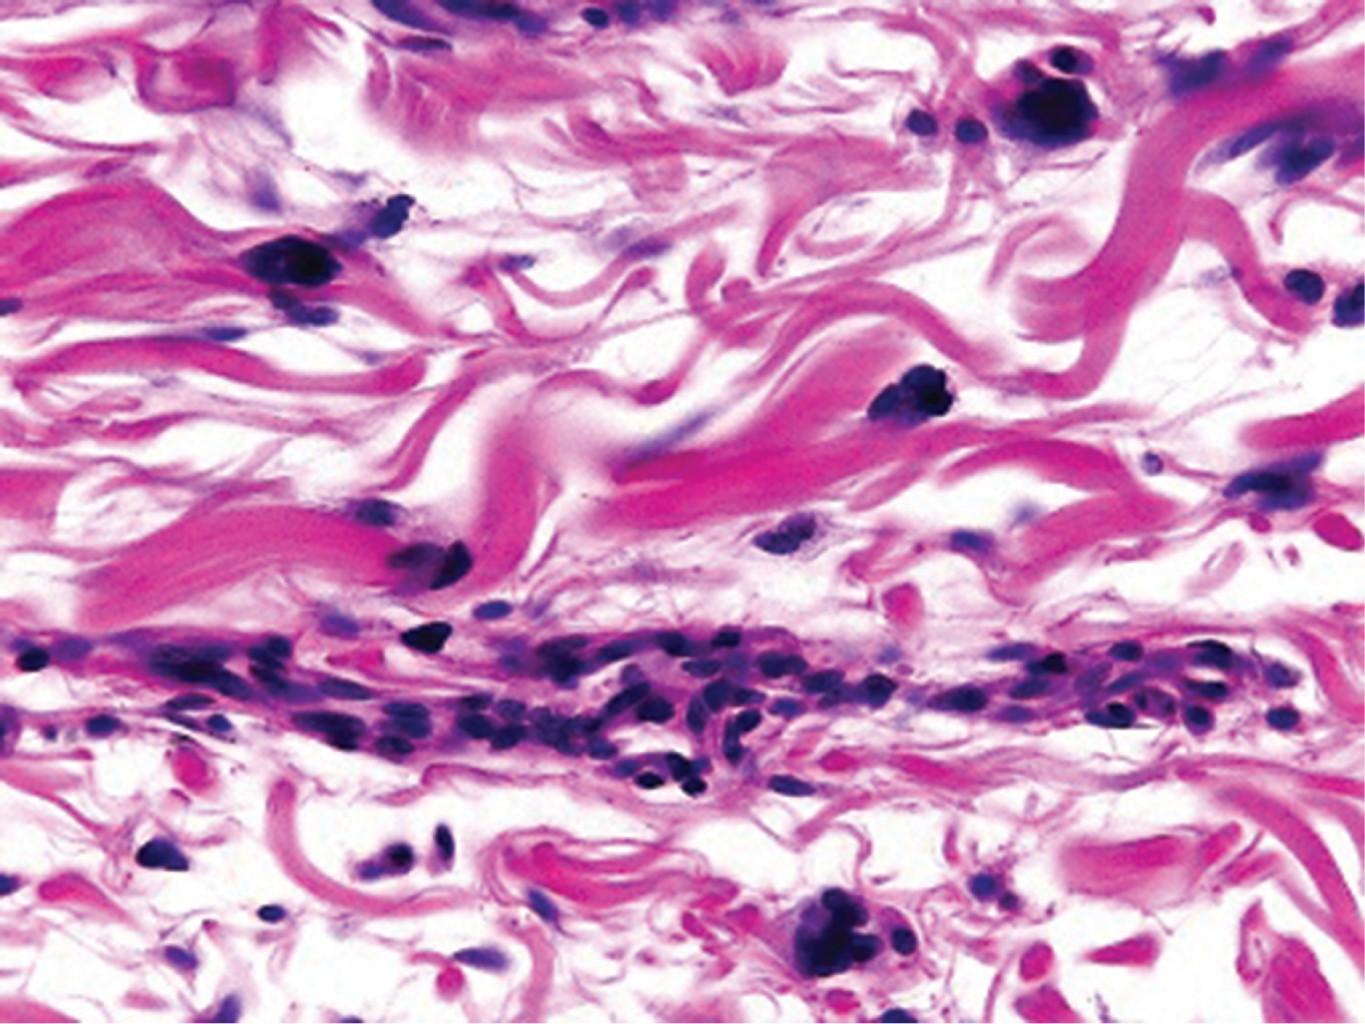

El estudio histológico es diagnóstico con los siguientes hallazgos: proliferación de vasos capilares y vénulas en la dermis superficial y media, cuyo endotelio es prominente y en ocasiones protruye hacia la luz, células multinucleadas que presentan citoplasma angulado con núcleos hipercromáticos en número variable, inmersas en un estroma fibroso.10,11 En la inmunohistoquímica, como es esperado, las células endoteliales expresan factor VIII, CD31 y CD34, mientras que los macrófagos, histiocitos y células multinucleadas expresan factor XIIIa, CD68 (variable) y vimentina.5 La dermatoscopía hasta el momento es inespecífica.12

Al interrogatorio, refiere haber iniciado hace cuatro años con "lunares" de forma lenta y progresiva. Sin tratamiento previo ni antecedentes médicos de relevancia. Clínicamente se hizo el diagnóstico de sarcoma de Kaposi vs histiocitosis y se solicitaron estudios paraclínicos, que descartaron infección por VIH u otras alteraciones. El estudio histológico mostró epidermis normal y en la dermis superficial y media presencia de vasos dilatados, fibrosis y células multinucleadas basofílicas con bordes angulosos (Figuras 3, 4 y 5).